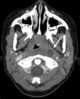

Enlarged lateral retropharyngeal lymph node